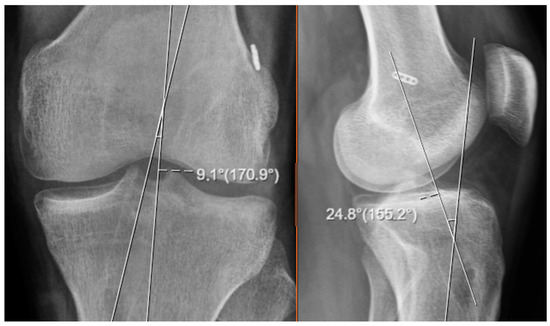

Figure 3. Image showing the measurement of tunnel angles on MRI.

The tibial tunnel angles derived through these three-dimensional calculations obtained solely from conventional roentgenographic images were subsequently compared with the actual tunnel angles measured directly on magnetic resonance imaging (MRI) scans. This comparison was performed to evaluate the degree of correlation, the extent of deviation, and the overall accuracy between the two distinct measurement approaches (see Figure 3). In the context of this study, the tunnel angles computed from roentgenograms were denoted by the symbols α and β, whereas the corresponding angles measured on MRI images were labeled as α′ (alpha prime) and β′ (beta prime), respectively. This symbolic differentiation was used throughout the analysis to clearly distinguish between values obtained by calculation and those determined via imaging.

For the MRI-based evaluations, oblique slices oriented parallel to the axis of the tibial tunnel were utilized in order to achieve accurate three-dimensional representations. These specific oblique images were carefully selected to align with the true orientation of the tunnel, allowing for more reliable angle measurement. In each case, two principal angular relationships were assessed: the angle formed between the tibial tunnel and the sagittal axis of the knee joint, and the angle formed between the tunnel and the anatomical longitudinal axis of the tibia. These MRI-based angle measurements served as the reference standard for assessing the validity and precision of the radiograph-based three-dimensional calculations.